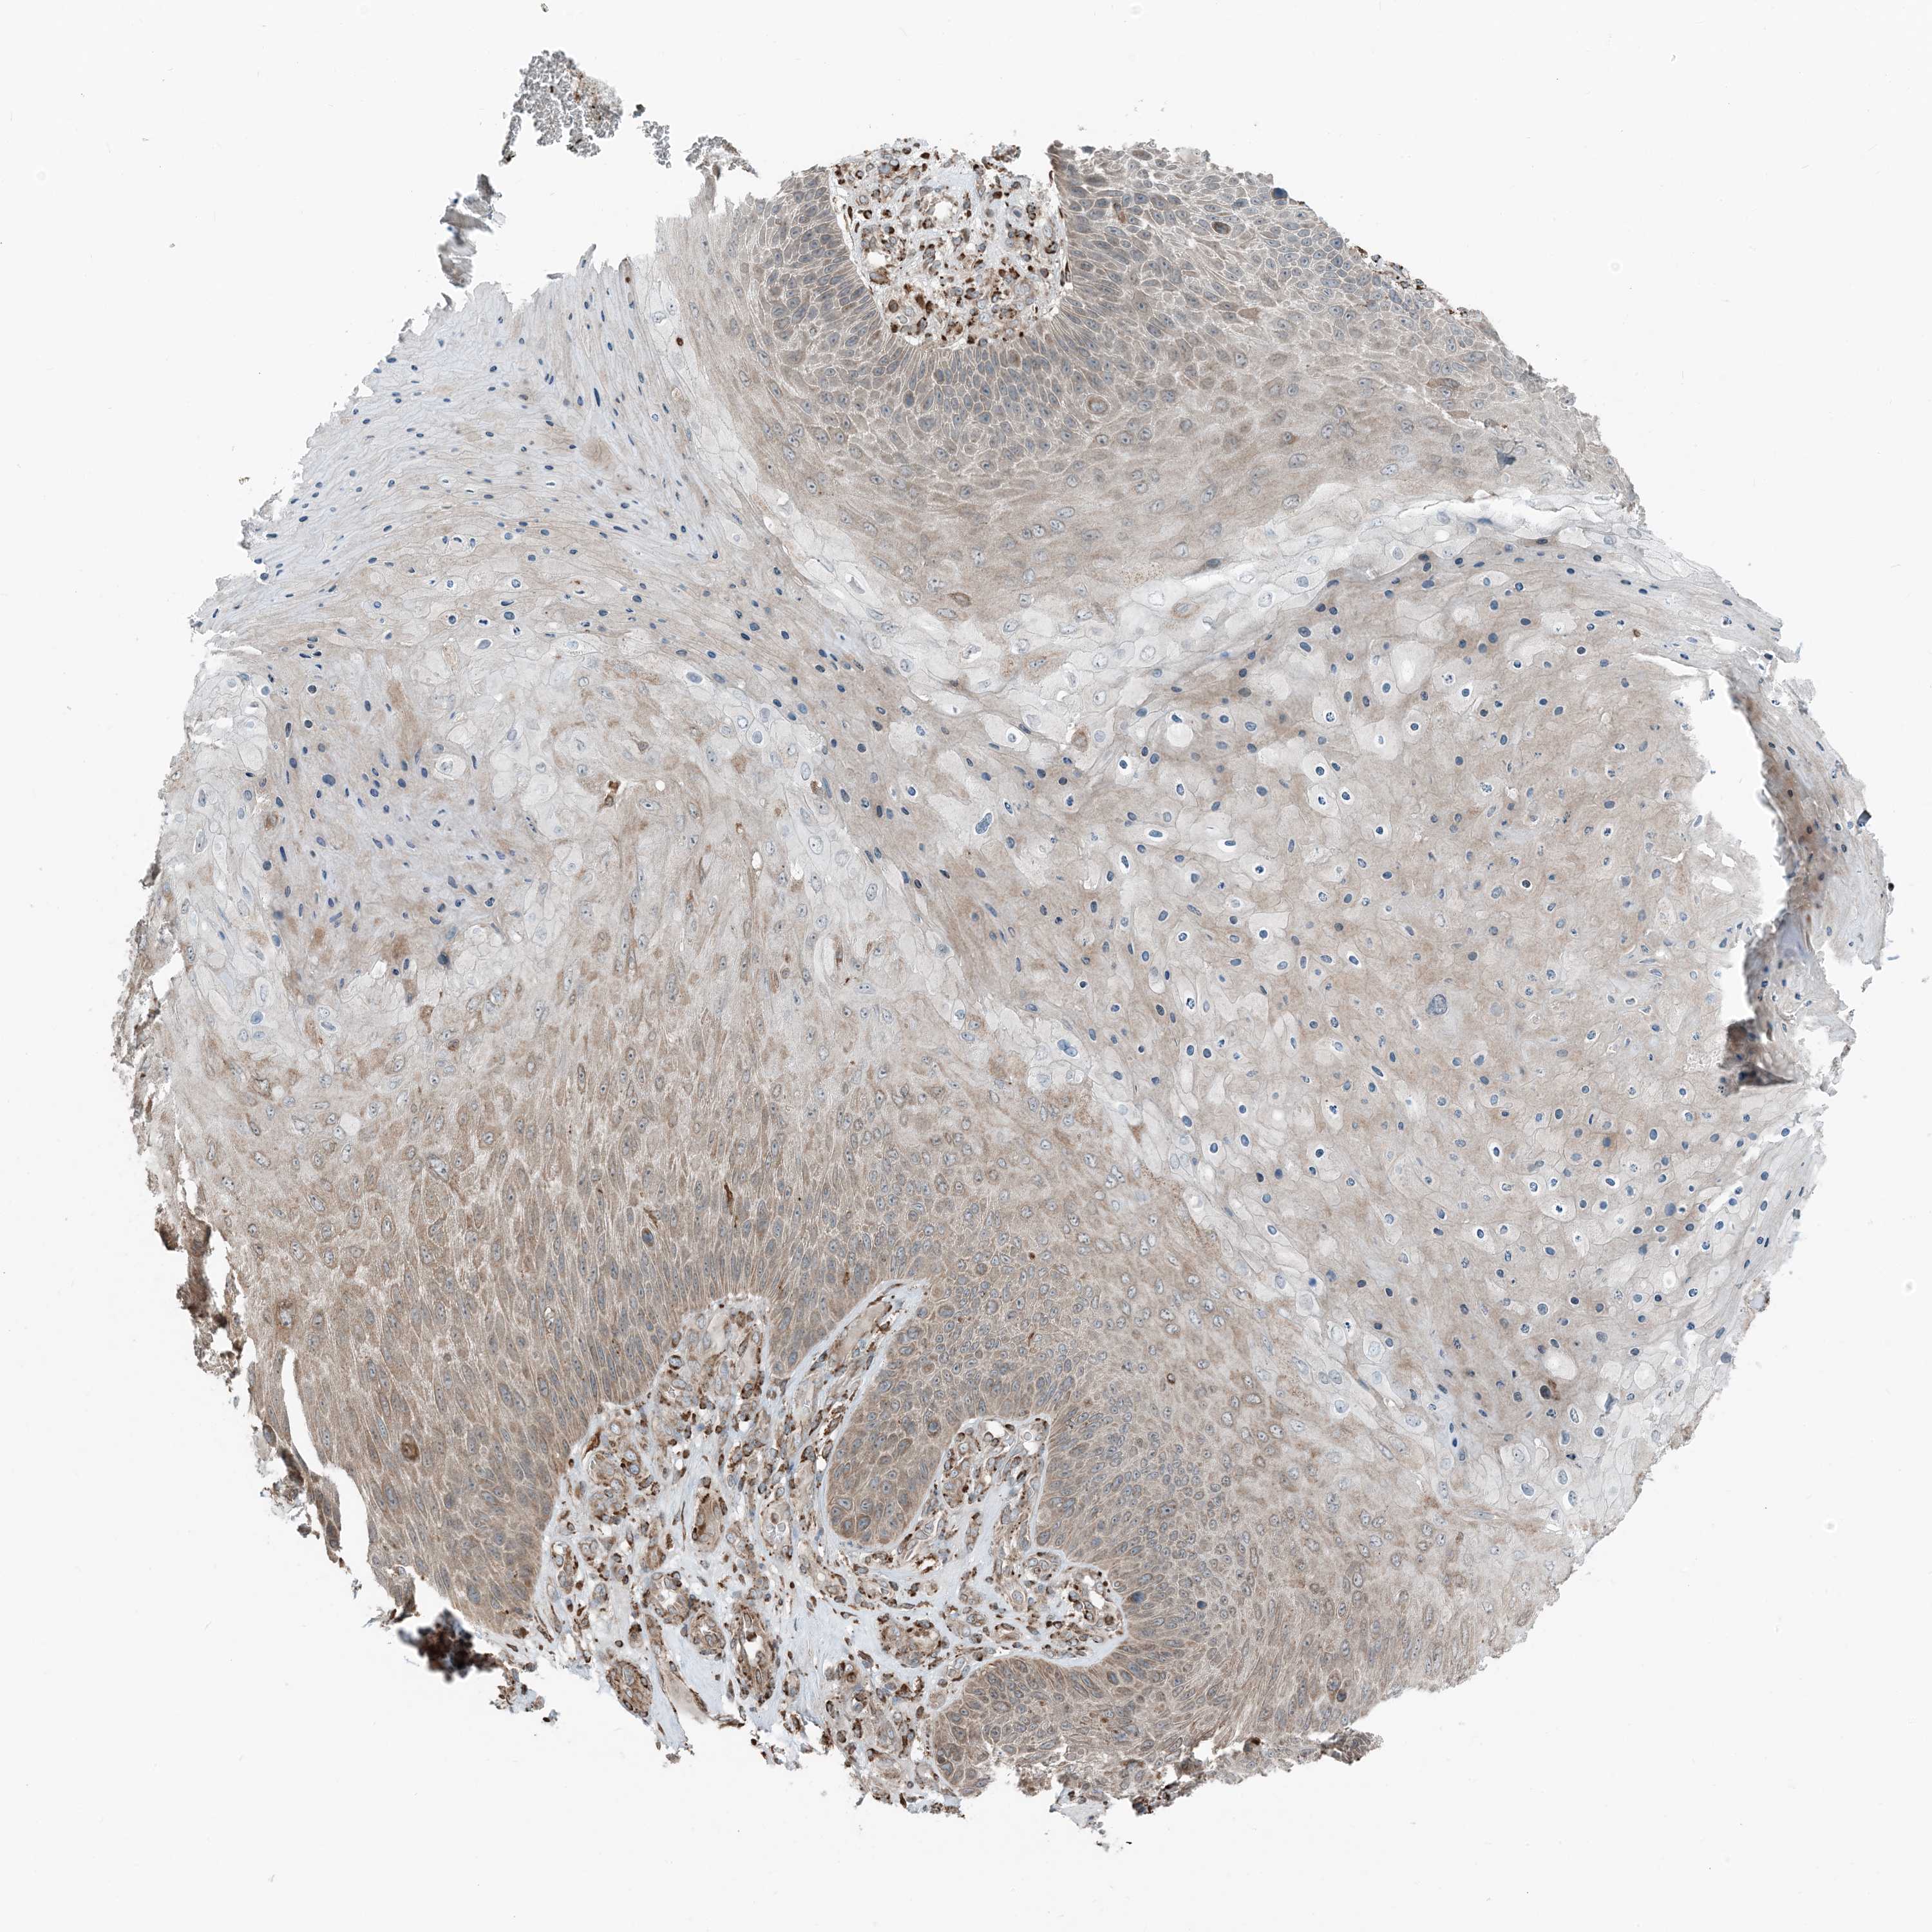

SKIN CANCER - Protein expressioni

A mouse-over function shows sample information and annotation data. Click on an image to view it in a full screen mode. Samples can be filtered based on level of antibody staining by selecting one or several of the following categories: high, medium, low and not detected. The assay and annotation is described here.

Each image is clickable and will lead to virtual microscopy that enables deeper exploration of all samples and also displays staining intensity scores, fraction scores and subcellular localization as well as patient and tissue information for each sample.

Antibody HPA035444

Staining

High

Medium

Low

Not detected

Intensity

Strong

Moderate

Weak

Negative

Quantity

>75%

75%-25%

<25%

None

Location

Nuclear

Cytoplasmic/membranous

Cytoplasmic/membranous,nuclear

Basal cell carcinoma